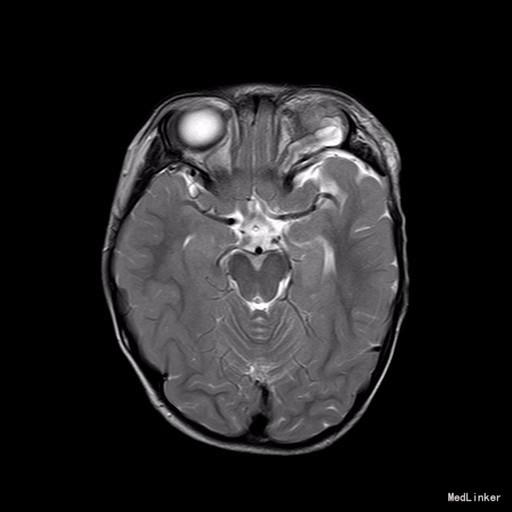

2岁9月患儿,因“左眼睑下垂1年余,头痛、呕吐8天”入院。家属1年前发现患儿左侧眼睑下垂,无法自行张开,一直未予特殊诊治。8天前患者哭闹频繁,诉头痛如爆炸样,剧烈难忍,并出现呕吐胃内容物数次,无伴抽搐、视力下降,无意识障碍。当地医院头颅MRI提示:左侧眼眶扩大,左侧眼球外上方泪腺区见一条状迂曲异常信号影,T1WI呈等信号,T2WI上病灶外缘呈高信号,内为等信号,增强扫描病灶中央呈条状明显强化影,边缘无明显强化,双侧大脑半球对称,灰白质对比正常,未见局灶性信号异常,左侧中颅窝前分蛛网膜下腔增宽,内为脑脊液信号;各脑室、脑池大小、形态均正常,中线结构居中,幕下小脑、脑干无异常,矢状面示垂体大小形态正常,未见局灶性信号异常;增强扫描未见明显异常强化。

查体见眼球稍向前突出,皮下可触及结节状软性肿物,缺乏边界,无搏动性眼球突出。左眼睑下垂,双瞳孔等圆等大,直径约2.5mm,光反射灵敏,眼球活动好,视力粗测正常,视野测试不能配合。

完善相关检查,在气管插管麻下行“左额眶部占位病变切除术”。术后病理诊断为“(左眼眶)丛状神经纤维瘤”。术后给予患儿脱水、营养脑神经、抗感染等对症治疗。复查CT未见明显异常。

患儿术后2周左眼睑下垂较术前好转。双侧瞳孔反射、眼球活动均无异常。 丛状神经纤维瘤主要发生于眼睑,在出生后或幼年时期即出现症状和体征。侵袭范围广泛,包括眼睑、眶内软组织、眶骨和邻近的脑、颞部等。眼部最早和最多见为上、下睑软性肥厚,皮下瘤组织增生,使上、下睑隆起。眼睑皮肤常有淡棕色色素斑,眼球向前突出和向下移位。眼球突出虽然很显著,但向眶内纳入并不困难。肿瘤组织可直接侵袭眶内各种结构,上睑提肌首先被波及,引起上睑下垂,上举不足或不能。MRI可准确显示病变的范围尤其显示病变与邻近结构的关系,也可清楚显示其他部位伴发的肿瘤,但难以清晰显示眶壁骨质改变。手术治疗是必要的,手术切除应注意以下问题:1.眼睑病变的切除;2.眶内病变的处理;3.提上睑肌的处理;4.眶骨缺失的处理。丛状型术前诊断容易,但治疗较为棘手,易复发。